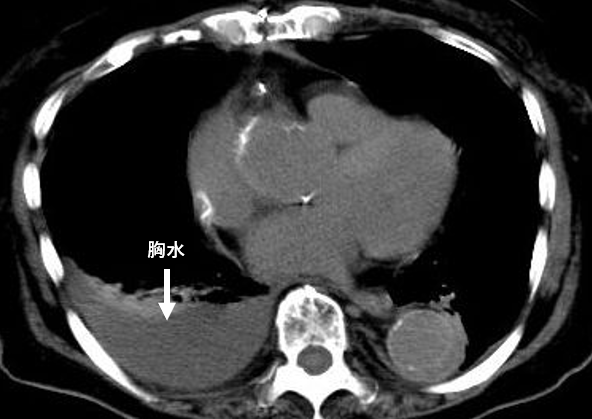

写真(2) 胸水患者のレントゲン写真

写真(2)は、僧帽弁閉鎖不全症により歩行時の息切れで入院した患者さんの胸部CTです。矢印が示すグレーの塊から、胸水が溜まっていることが分かります。